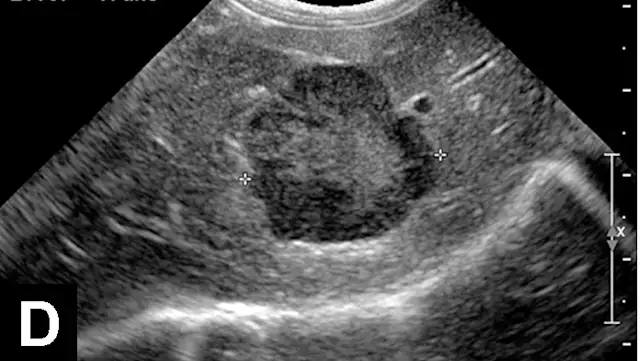

Figure 1A

In each of these cases, histologic diagnosis was made using fine-needle aspirates of the liver (vacuolar hepatopathy, hepatic lipidosis, acute severe neutrophilic hepatitis, respectively). Transverse image (A) of the left side of the liver in a normal dog showing hepatic vein (arrows) and portal vein (arrowheads). Hyperechoic liver (B) secondary to glycogen accumulation resulting from Cushing’s disease in a dog. Note the decrease in portal vascular markings. Hyperechoic and hyperattenuating liver (C) secondary to hepatic lipidosis in a cat. Note the hypoechoic falciform fat in the near field (≤1.5 cm deep) relative to liver echogenicity. In addition, there are some contact artifacts resulting in hyperechoic lines as well as the normal lines of abdominal musculature in the extreme near field (<0.5 cm). In normal cats, falciform fat and hepatic echogenicity are isoechoic to each other. In the far field, hyperattenuation of the ultrasound beam results in image dropout (starting at a depth of 3.5 cm). Hypoechoic liver (D) secondary to acute hepatitis in a dog. Note the marked decrease in echogenicity relative to the spleen.